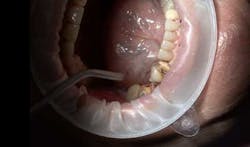

Fig. 3: Dry the preparation area that is going to be impressed.

Fig. 4: Extruding Virtual XD onto the preparation and note thumb support and guidance for controlled rapid delivery.Insert the tray far enough into the mouth so you can seat it straight up or down over the teeth (Figs. 5 and 6). When the tray material is placed, the material starts to penetrate and flow deep into the sulcus, capturing the necessary detail. Hold the tray in place for the minimum set time, which can range from 2-and-a-half minutes for fast set to 4-and-a-half minutes for regular set with this material. After the set time, check the material to verify the tray material has set and remove the tray very slowly, not from the handle, but rather first breaking posterior seal. This is especially important with double cord technique to avoid marginal tears from possible cord attaching to material.